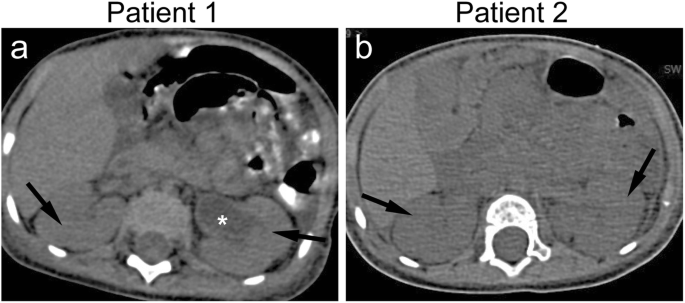

Chest CT scan demonstrated patchy shadows, consolidation, and pleural effusion in the 3 patients (Fig. 2a–c). Ascites and enlarged kidneys were observed in the two infants (Fig. 3a, b).

Fig. 3

figure 3

Axial abdomen CT scan images of patients 1 and 2 (a, b) showing enlarged kidneys (arrows). Hydronephrosis of the left kidney can be observed in patient 1 (star). The hydronephrosis disappeared before discharge